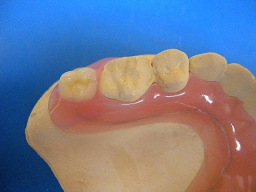

ホワイトコートは、以下のような色調で、自然ではありませんが、多くの方に喜んでもらっていました。これまでは他に方法がなかったので、やむおえません。

このホワイトコートは、3ヶ月くらいで部分的にはがれてきますが、運がよければ1年以上はがれずに維持できています。歯は全く削りません。

術前 ↓

術後

見た目は、やはり グラディアダイレクトには及びません。

今回のグラディアダイレクトは、歯の表面の処理方法や接着方法がホワイトコートよりも優れているので、数年は問題なく維持できると思っています。

おそらくこれからは、見た目の自然さから、ホワイトコートを選ぶ患者さんは減り、グラディアダイレクトに変わっていくと思います。